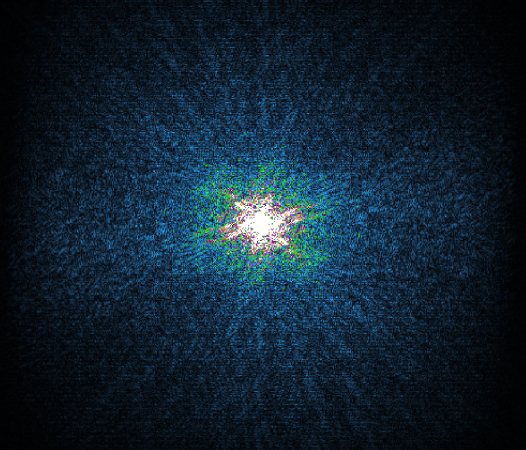

K-space compressed sense

The Compressed SENSE reconstruction then uses iterative, knowledge-based algorithms to fill in the empty lines in k-space (bottom left). This removes the artifacts while keeping the final image fully consistent with the acquired data (bottom right).